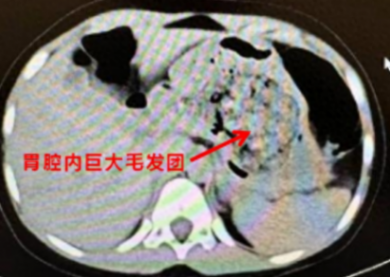

医生听到这里豁然开朗,原来在ct阅片的时候,发现了孩子胃里面有一团密度较高的团块,结合母亲提供的病史,医生断定孩子长期吃头发导致了胃内毛发成团,这也是这次腹痛的原因。

胃里巨大的毛发团

得出了初步诊断后,医生立即安排孩子住院,联系消化内科医生做胃镜检查,如果能够明确诊断,可以先尝试胃镜下取出,达到“无创”的效果。结果,当胃镜进入的瞬间,所有人都惊呆了,孩子胃内的毛发包裹食物残渣形成了一个巨大的团块,充满整个胃腔。